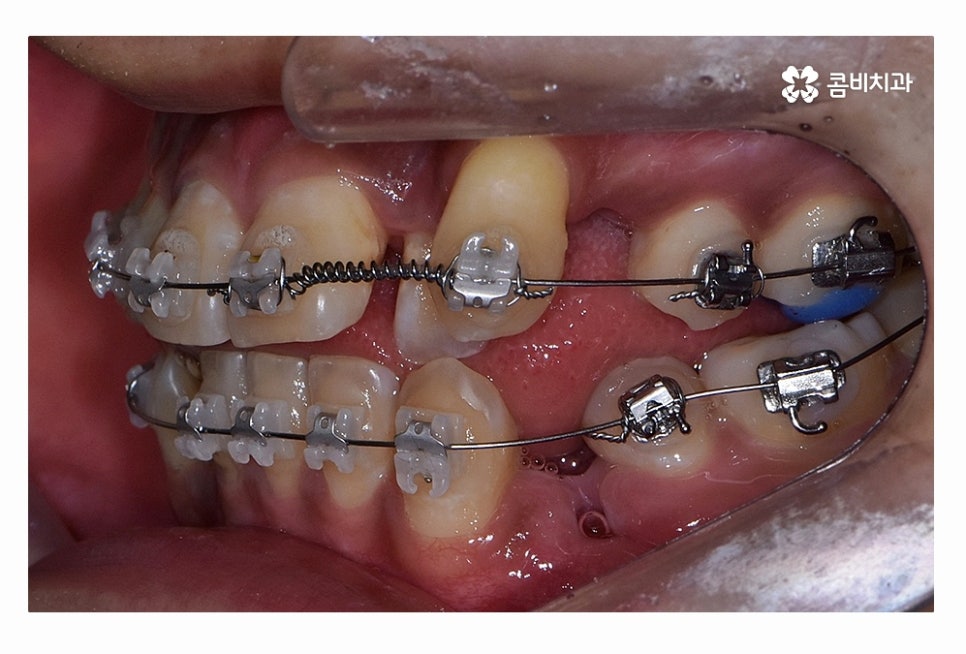

오늘 보시는 환자분의 사례처럼 덧니가 치아끼리 겹쳐 있는 경우에

치아의 이동 공간 확보를 위해서 덧니 발치 필요한 사례였으며

교합과 치아교정 후 얼굴 변화를 고려할 때도 치아교정 과정에서

발치가 필요한 사례였다고 볼 수 있어요.